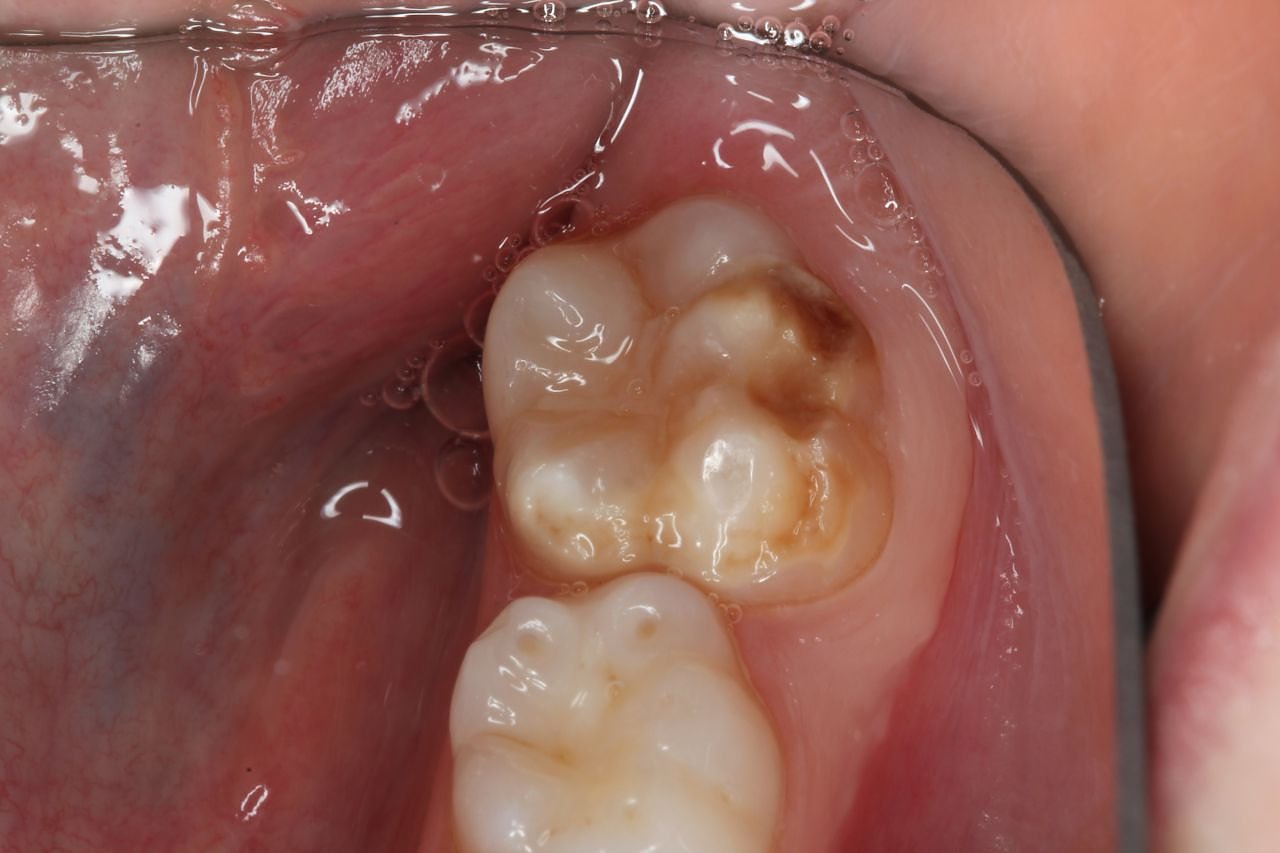

Bei Kreidezähnen handelt es sich eine Schmelzbildungsstörung, die meist an den ersten bleibenden Backenzähnen auftritt, häufig auch an den bleibenden Frontzähnen. Milchzähne können ebenfalls betroffen sein. Es bilden sich weiße bis gelblichbraune Flecken – je größer und dunkler die verfärbten Stellen sind, desto stärker ist die Störung. Bei schweren Fällen ist der Zahnschmelz stark geschwächt und bricht ein, daher auch der Begriff Kreidezähne. Bei den schwächeren Ausprägungen sind die Zähne nur verfärbt. In den meisten erkannten Fällen von Kreidezähnen haben die jungen Patienten starke Schmerzen, insbesondere beim Zähneputzen und Essen. Daraus können sich Ängste entwickeln. Zudem können unbehandelte Kreidezähne langfristig zu schlechter Mundhygiene und Karies führen, verdeutlicht Birgit Dziuk. Eltern müssten sich aber keine Vorwürfe machen. Bei Kreidezähnen handle es sich um Schädigungen der Zähne, die nicht durch mangelhafte Mundhygiene entstehen. Wichtig sei, dass die Störung frühzeitig erkannt und behandelt wird.